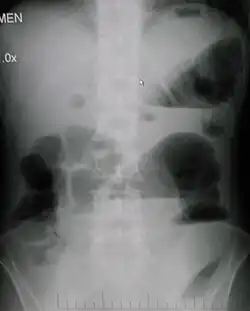

W przeglądowym zdjęciu RTG jamy brzusznej w pozycji stojącej lub bocznej widoczne są poziomy płynu w rozdętych pętlach jelitowych, co jest efektem rozdzielenia treści jelitowej na frakcję gazową i płynną. Poziomy płynów o długości przekraczającej 2,5 cm są uważane za patognomiczne dla niedrożności jelit[9]. W niedrożności mechanicznej z zatkania rozdęcie pętli pojawia się powyżej miejsca zatkania. W niskiej niedrożności rozdęte pętle nakładają się na siebie utrudniając rozpoznanie. W niedrożności zlokalizowanej w jelicie grubym i wydolnej zastawce krętniczej-kątniczej rozdęte jest tylko jelito grube[18].

Niedrożność z zadzierzgnięcia daje podobny obraz, rzadziej pojawia się obraz pseudoguza lub pętla z poziomem płynu i gazu z nakłądającymi się na siebie ścianami (obraz "ziarna kawy"). W niedrożności porażennej poziomy płynów są mniej liczne i występują na całej długości jelita[18].